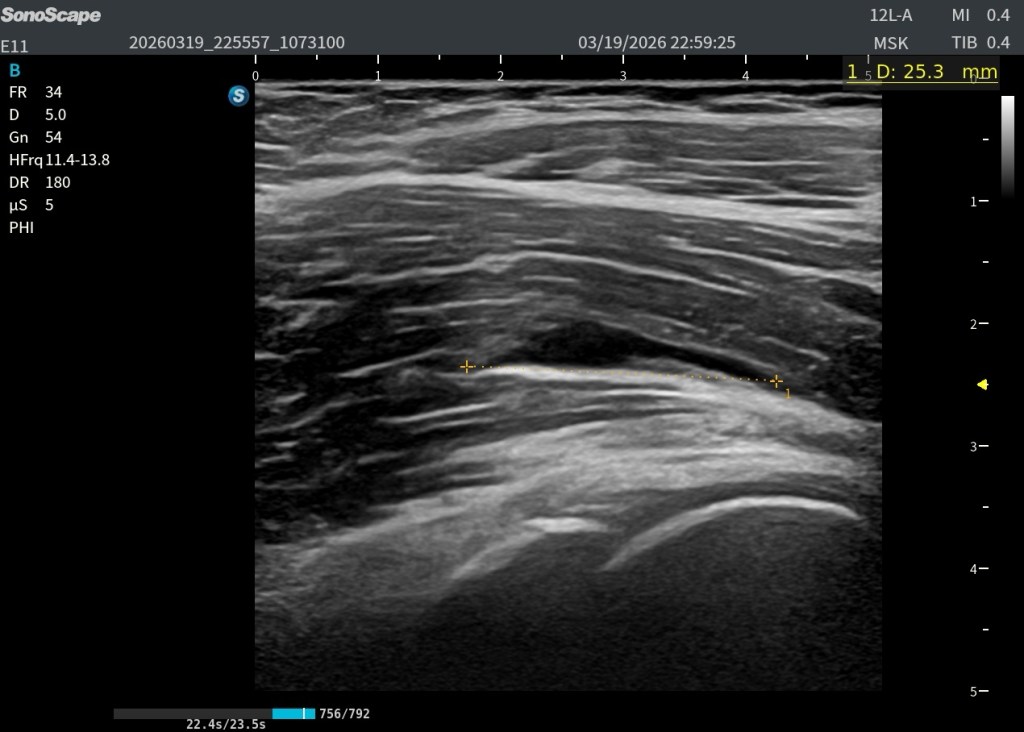

En eje longitudinal (eje largo – línea roja): Imagen anecoica alargada Localizada en las fibras profundas del psoas Con una longitud aproximada de 2,5 cm En eje transversal (eje corto – línea amarilla): La lesión se reproduce claramente, confirmando su existencia siempre en dos ejes. Si no lo veo en 2 cortes, no existe.

👉 La visualización en ambos planos es clave para confirmar que no se trata de un artefacto.

Y comparar…eso siempre nos va a dar un plus.

Rotura de las fibras internas posteriores del psoas ilíaco izquierdo, con colección anecoica compatible con hematoma.